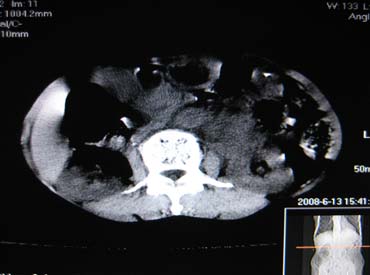

女,65岁,左上腹痛。

肝脏占位  脾脏及胰腺病变   请提供病史

肝脾胃左肾胰都显示不正常啊

病史不详,肝、脾、胰都有占位,谁是原发?

胰腺癌伴脾脏侵犯并肝内转移可能性大  建议增强扫描  否则没有确凿的依据

考虑姨尾癌,腹膜后转移\\肝转移

没有病史,没有强化,那就只有猜了,我看病灶很像肝、脾及腹腔多发脓肿,这只是我的意见,

图像欠清,病灶与胃脾胰肾上腺关系显示欠清,建议增强,肝脏考虑转移瘤.

多脏器占位,腹膜后淋巴结增大,淋巴瘤?建议增强扫描